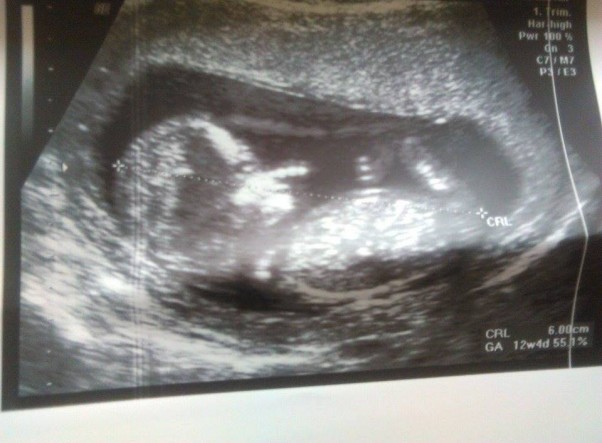

To moje małe szczęście. Pan doktor podejrzewa, że to chłopiec. więc rośnie kawaler ;-) 6 cm szczescia